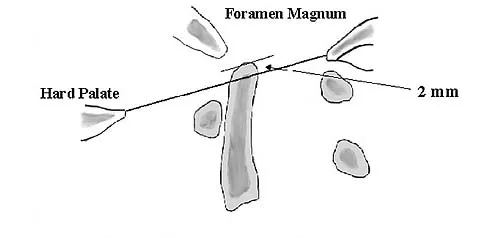

Figures 9a and 9b show the spinal radiographs of a 3-year-old child with short limb dwarfism. The lateral radiograph is obtained with maximal lumbar extension. Management should consist of